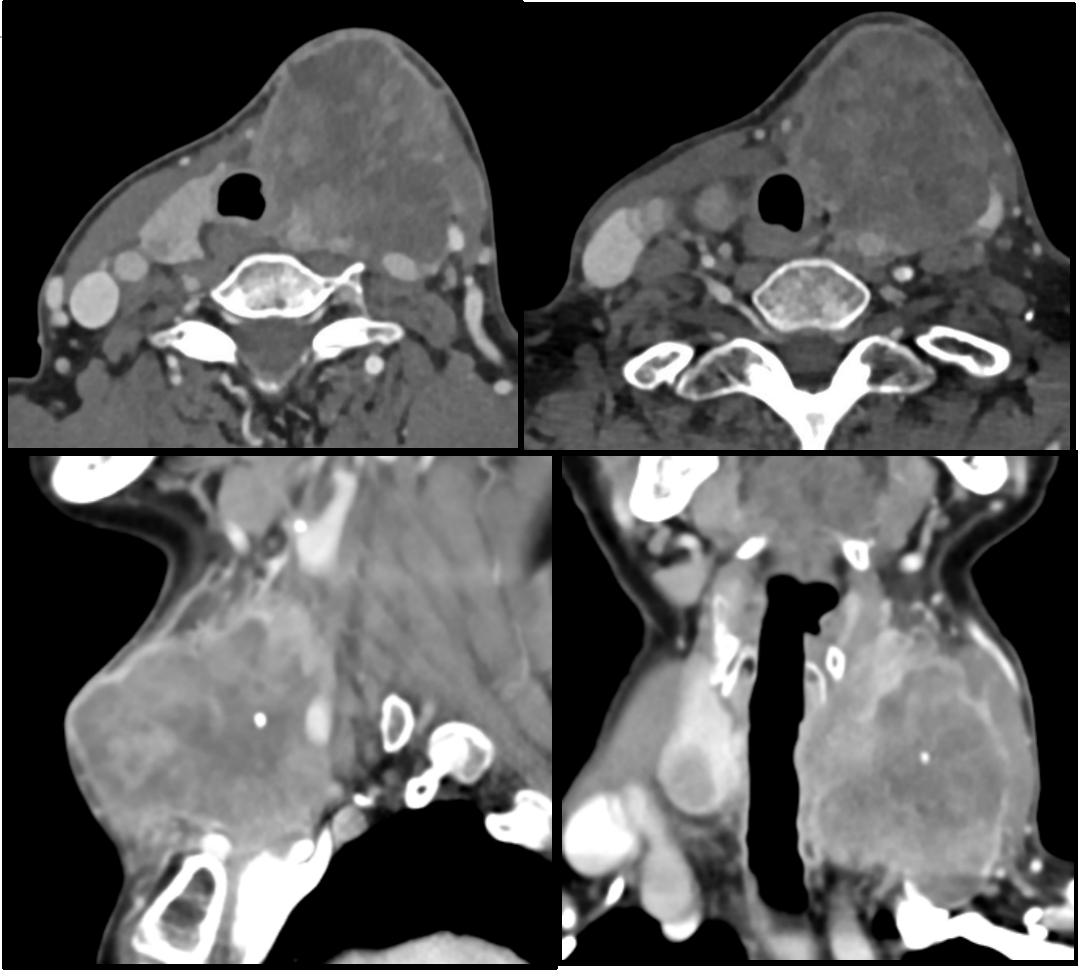

甲状腺癌有活30年的吗

甲状腺癌患者在经过规范治疗后,有活40年的可能甲状腺癌的预后情况与其病理类型密切相关分化型甲状腺癌如乳头状癌和滤泡状癌的恶性程度较低,生物学行为相对温和即使出现颈部淋巴结转移或远处转移,通过规范的手术放射性碘治疗以及...